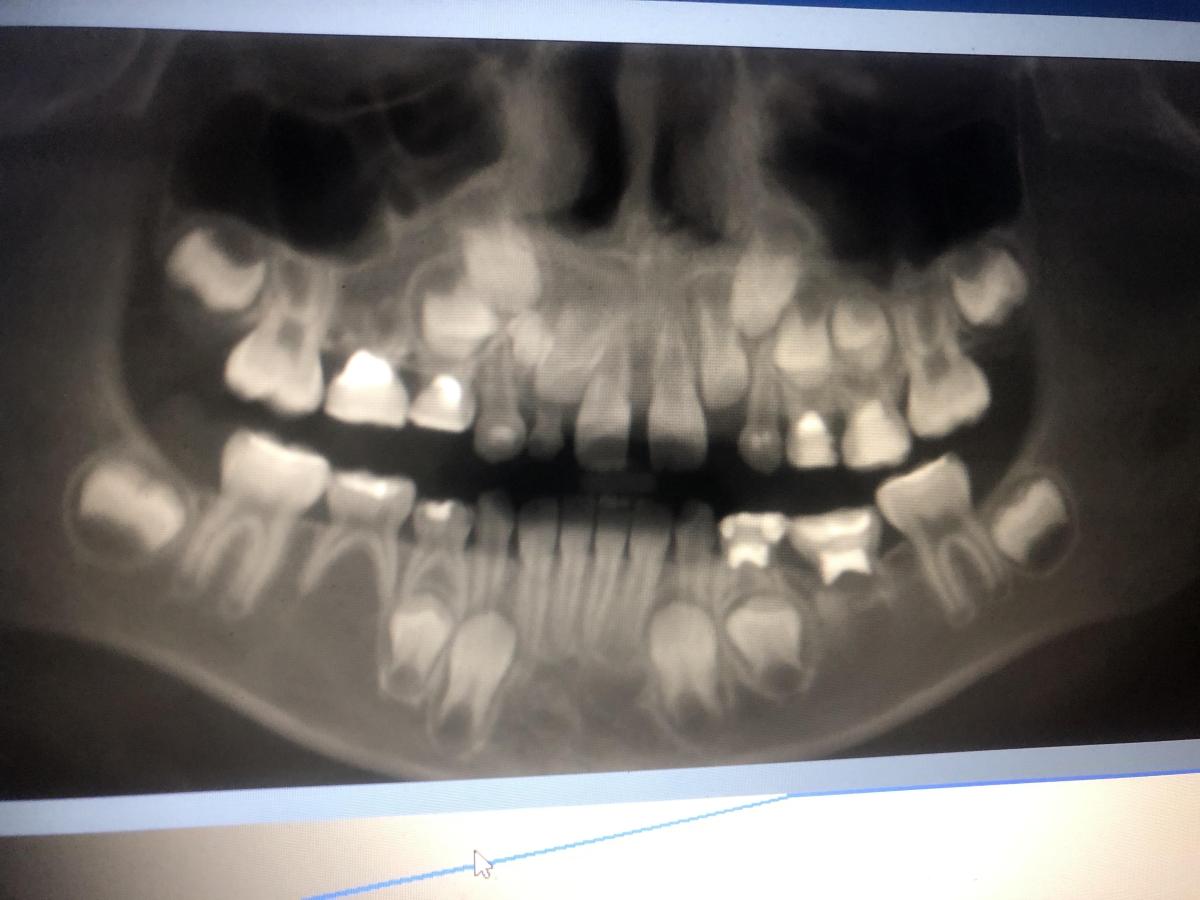

Здравствуйте, Ребекку 7 лет. Отсутствуют нижние зачатки 5 зубов. Верхний зачаток пятерки в недоразвитом состоянии и перевернут . Что с ним будет? Возможно ли что вырастет как надо? И основной вопрос- верхний клык (снимок прилагаю) между молочным и коренным обнаружено какое-то образование- это лишний зуб? Как его удалять? Вырывать молочный клык сейчас , далее удалять лишний и уже после ждать прорезывания постоянного? Или ждать пока молочный сам выпадет?